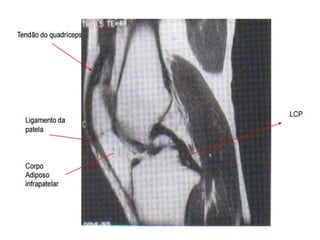

T1 NO JOELHO

 Utilizada para verificar anatomia muscular, óssea e

principalmente menisco.

 A gordura fica branca, fornecendo contraste para o

tendão e o músculo.